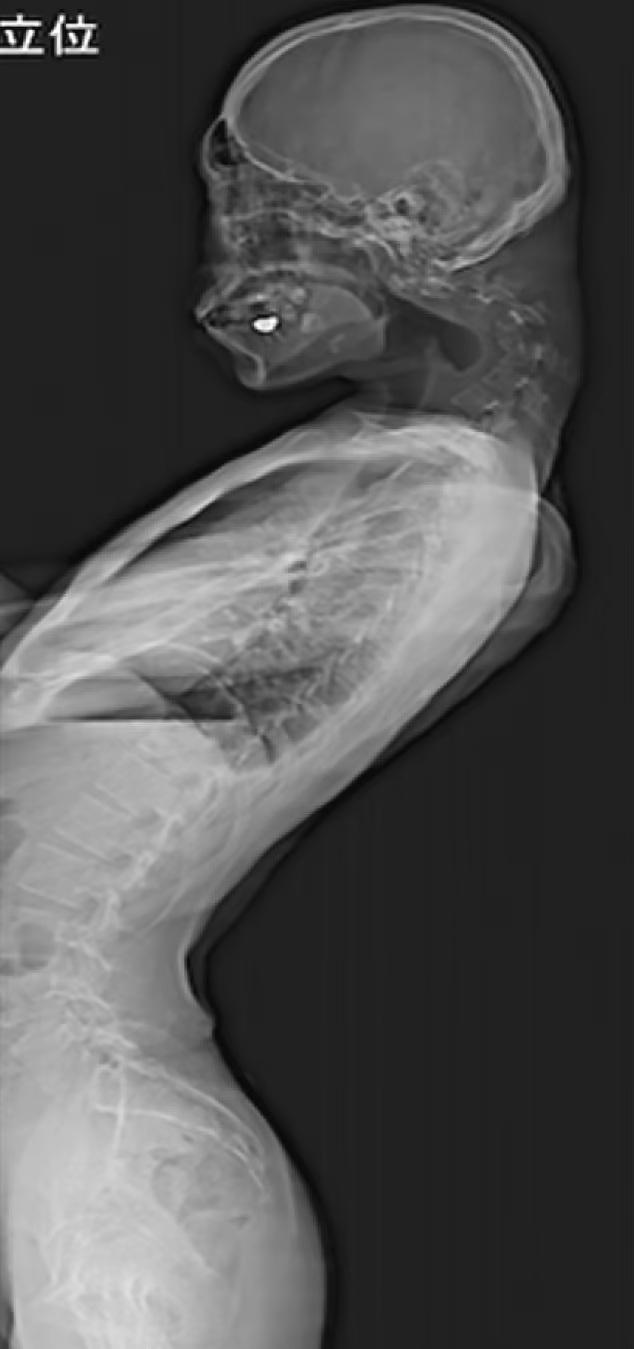

日本一名25歲男子長期低頭玩手機遊戲導致嚴重垂頭症,頸椎向前90度彎曲。(互聯網)

英國《每日郵報》稱,這宗恐怖「垂頭症」(dropped head syndrome)病例於2023年在整形外科期刊JOS Case Reports刊登,X光片可見患者的頸椎明顯90度彎曲,那名男患者頭向前垂,後頸有一角型物體凸出。報道指,患者幼時活潑開朗,但青少年時期遭欺凌變成宅男,退學後躲在房裡數年。他在房間裡只低頭玩手機遊戲,結果導致嚴重垂頭症。除了外觀問題,該男子嚴重頸痛長達半年,也開始抬不起頭,加上吞嚥困難、體重暴降,最終尋求治療。